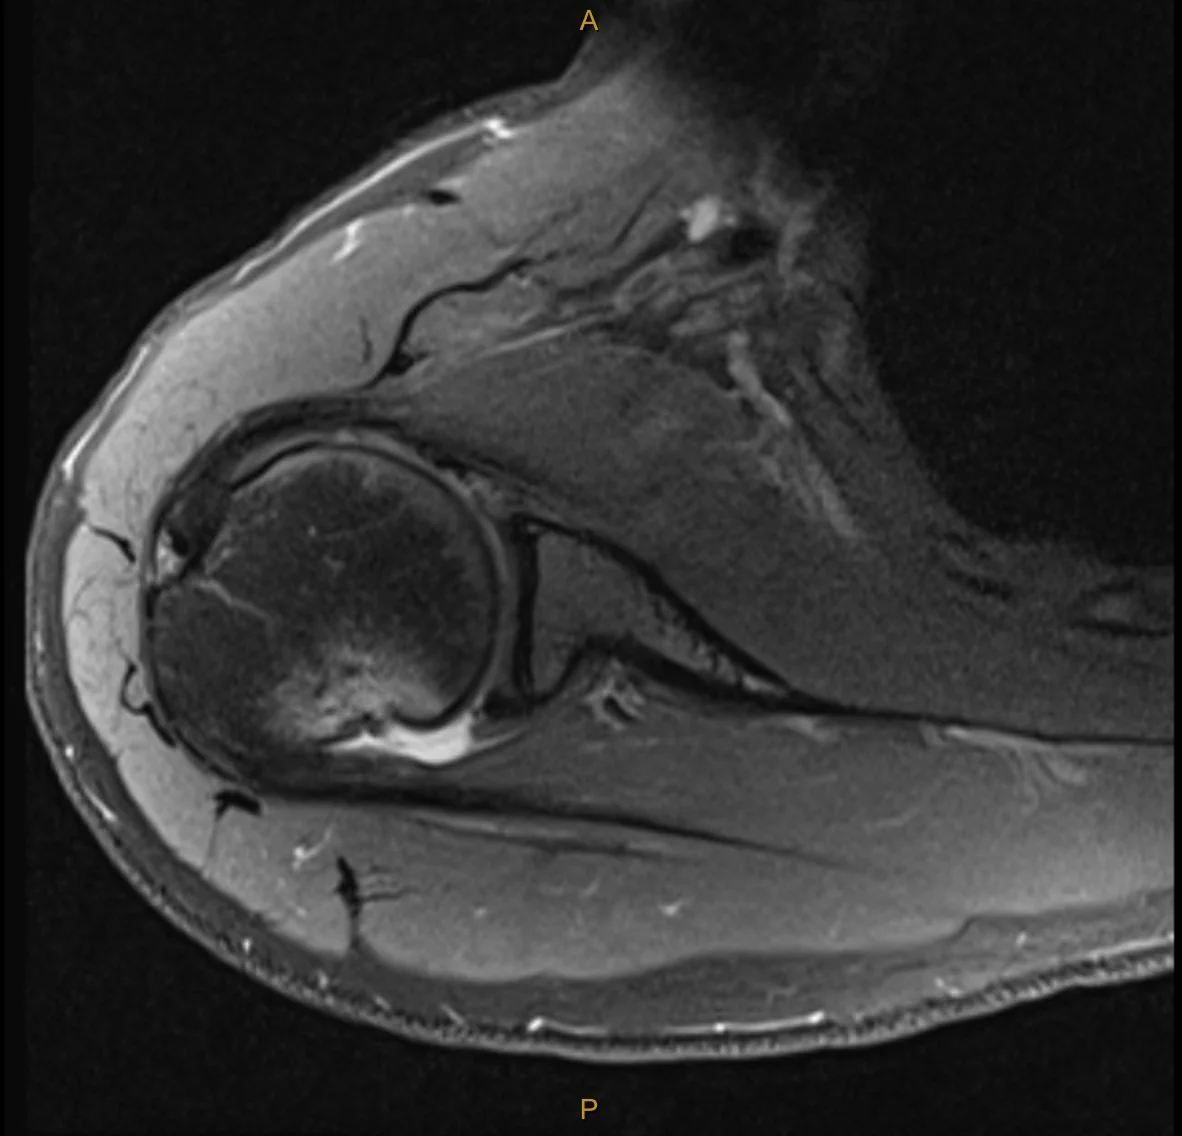

My clinical impression was the Ms C’s presentation was consistent with the event of an anterior dislocation and that MRI would best visualise the extent of tissue pathology. The report was incredibly detailed, and yet, there was additional structural damage which was not found until months later during surgery. The key findings (and my thoughts on their significance) are below:

Broad Hill-sachs lesion with underlying bone marrow oedema in keeping with recent anterior macroinstability event.

Impact fracture of the humeral head from contact on the glenoid. This fracture and indentation into the humeral head does not improve unless operated on and can lead to further instability and dislocation in positions of elevation and external rotation as the humeral head moves past the glenoid. This particular part of the injury is what is managed with the “remplissage” technique. (indication for surgery).

The bone marrow oedema can take between 3-6 months to settle (indication for wait and see).

Mild complex tear of the inferior to anterosuperior labrum extending from roughly the 6 o’clock position to the 10 o’clock position. [Fibrocartilaginous Bankart lesion]

No accompanying osseous Bankart lesion. [The glenoid was not fractured during dislocation]

There is slight elevation of the anterior glenolabral periosteum, consistent with some periosteal stripping.

No significant glenohumeral chondropathy.

Small joint effusion.

Intact cuff.

Not reported until surgery:Posterior labral tear and anteriorinferior chondral damage.

In addition to the exact MRI findings for this case, I have also added some images which outline the variants of a Bankart lesion and Hill-Sachs lesion below.